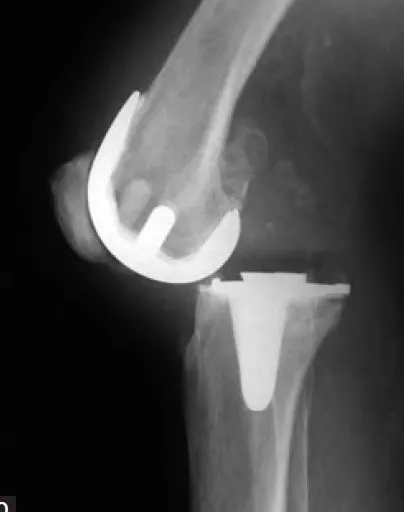

Joint Instability

Repairing or replacing implants impacted by weakened or damaged bone.